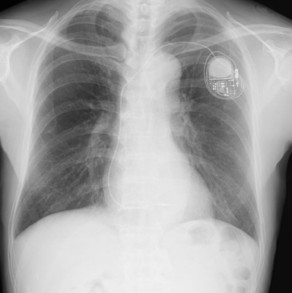

恒久的ペースメーカー植え込み術や電池交換に対応できるようになっております。MRI対応ペースメーカーデバイスを使用しており、当院ではMRI対応ペースメーカーであればMRI撮影も可能です。リード耐久を考慮し全例胸郭外穿刺にてリード挿入を行っております。